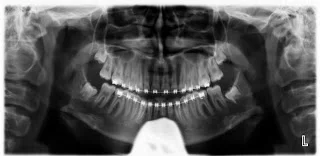

Below is an x-ray of a 16 year-old with roots about 1/3rd formed.  This is a great time to get them evaluated by an oral surgeon.